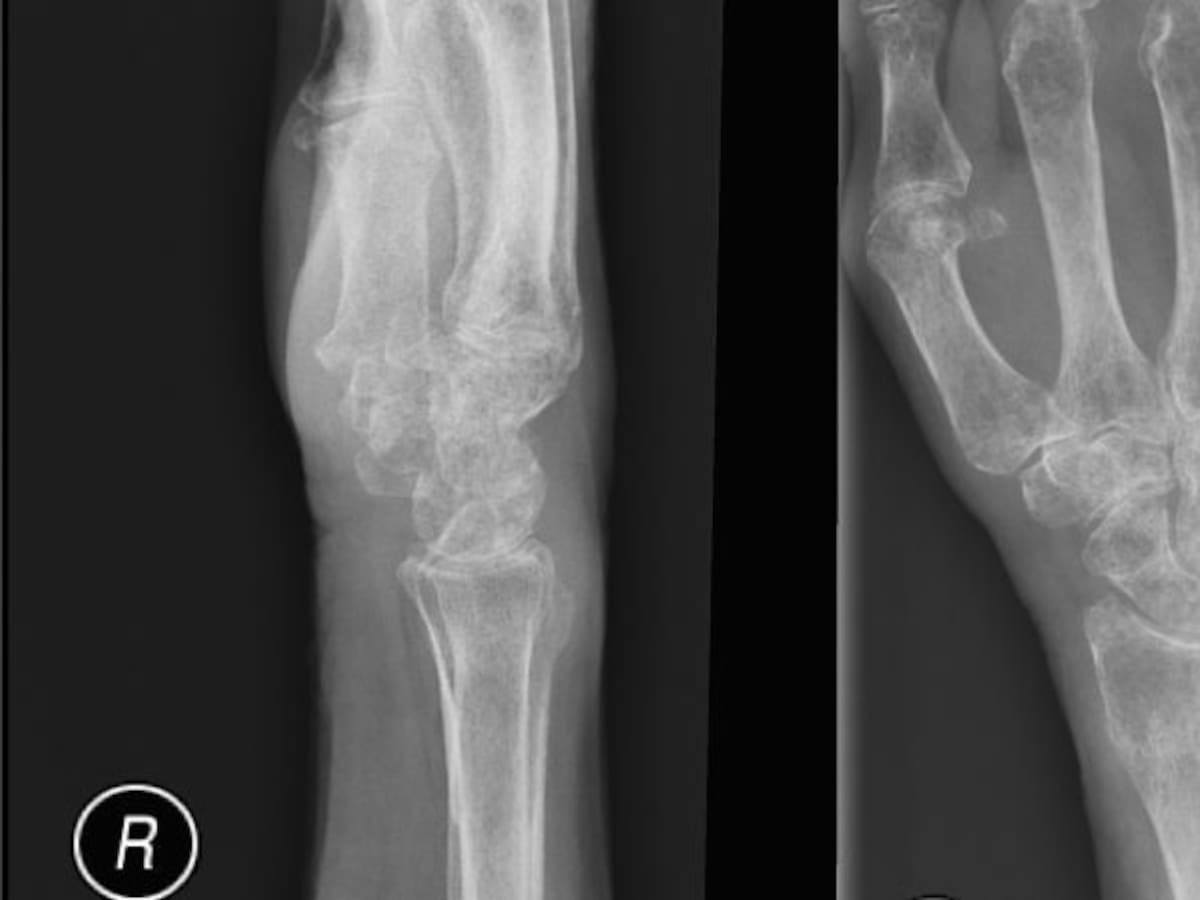

¿Ha perdido talla en su estatura? Puede tener la enfermedad de los huesos

Si ha perdido talla en su estatura o ha empezado a encorvarse, puede estar presentando osteoporosis, una enfermedad silenciosa que debilita los huesos, ¿Cómo reconocer esta enfermedad y cómo prevenirla?